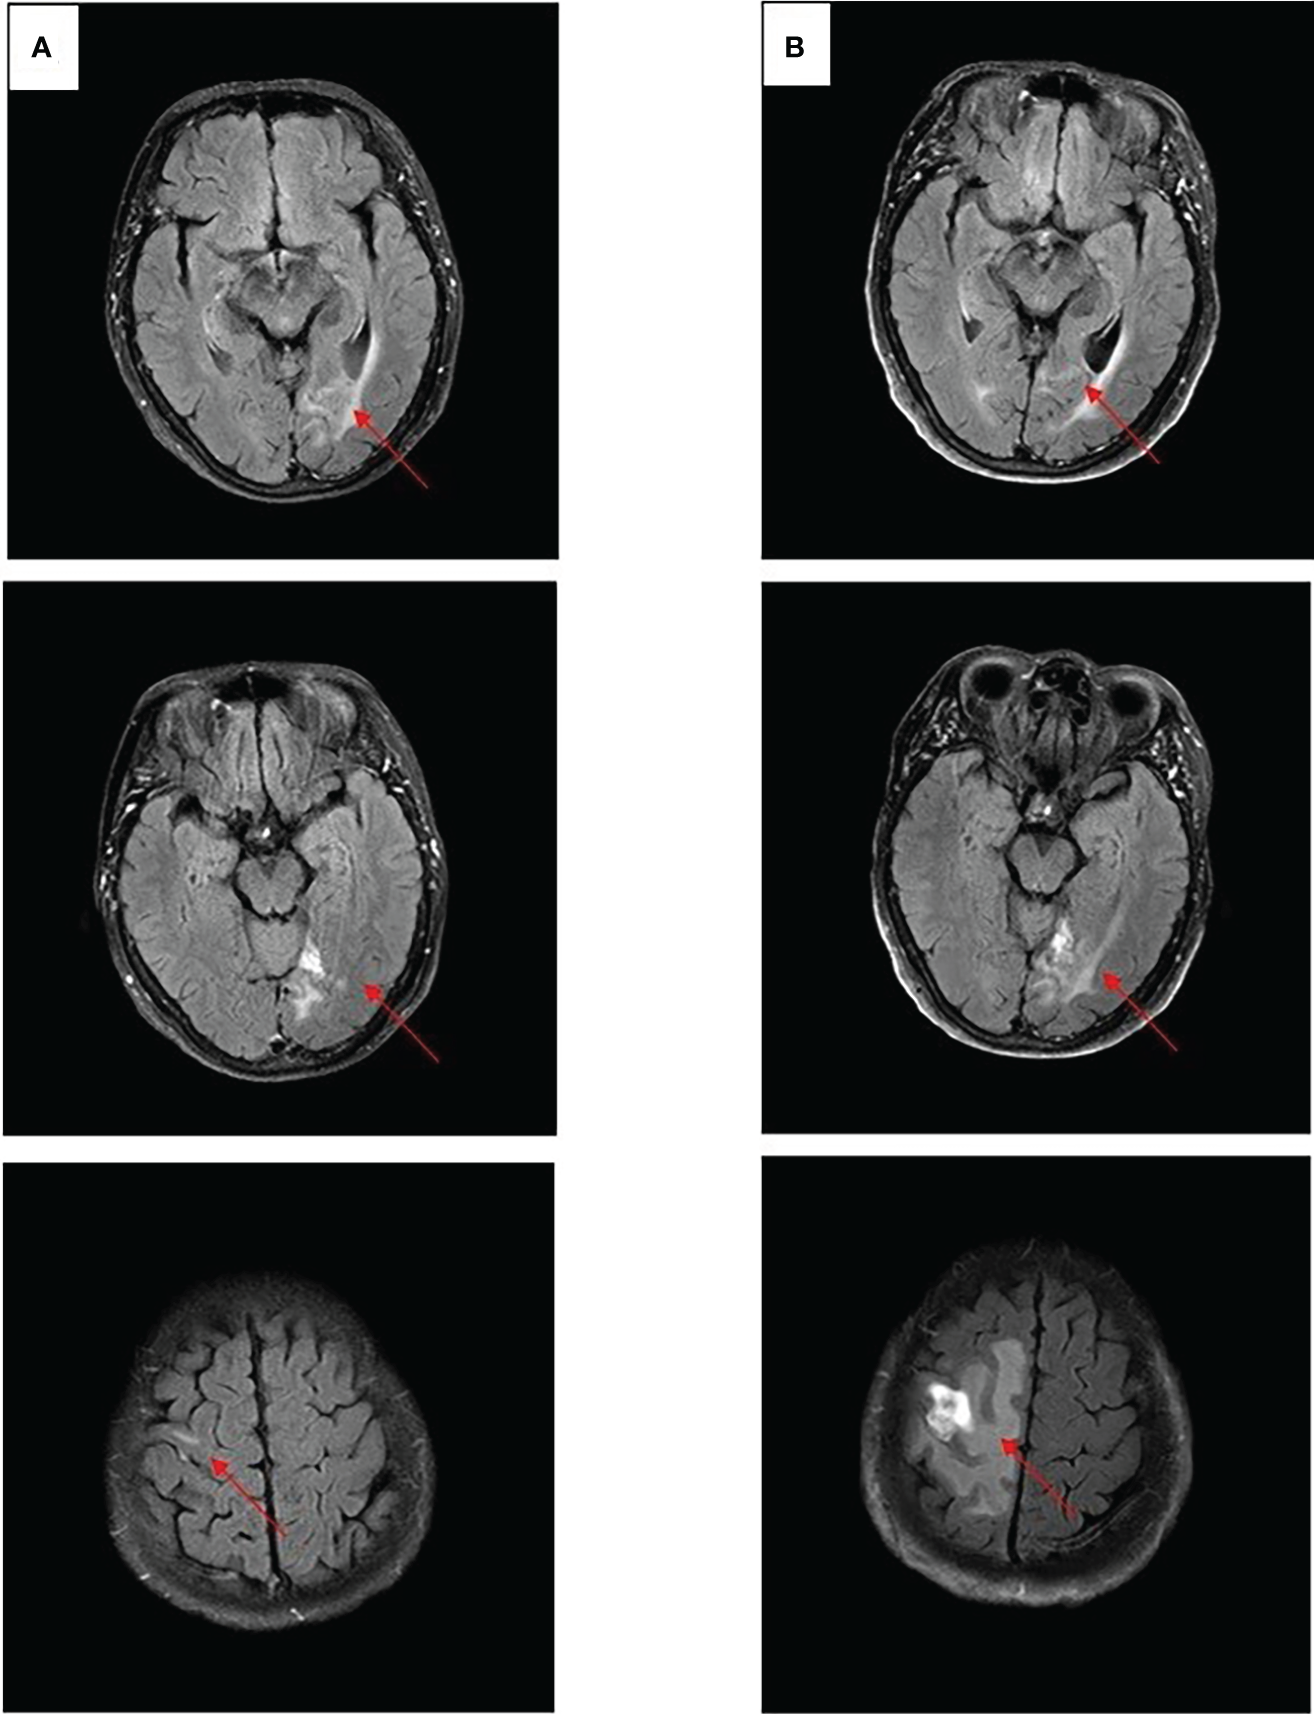

After experiencing dizziness and headache, the patient was reexamined by brain MRI on 19 January 2021, which revealed a new brain metastasis in the left occipital lobe (Figure 3A). The patient refused radiotherapy, chemotherapy, and immunotherapy, and started oral dacomitinib treatment with a dose of 30 mg daily. After several days, the patient’s neurological symptoms were significantly relieved. The patient underwent MRI 2 months later, and found that the lesion was significantly reduced, the efficacy achieved partial response (PR) (Figure 3B), and follow-up MRI at 4 and 6 months showed that the lesion continued to shrink and almost disappeared (Figures 3C, D). The patient continued to receive dacomitinib until new right parietal lobe brain metastases were identified on 23 June 2022 (the cutoff day, Figures 4A, B), and the progression-free survival (PFS) was 17 months (Figure 5). No obvious adverse reactions have been observed during the patient’s medication.

Figure 4

Craniocerebral MRI about clinical response to dacomitinib therapy at different times. (A) Brain metastases still PR after 12 months. (B) Brain metastases PD after 17 months.